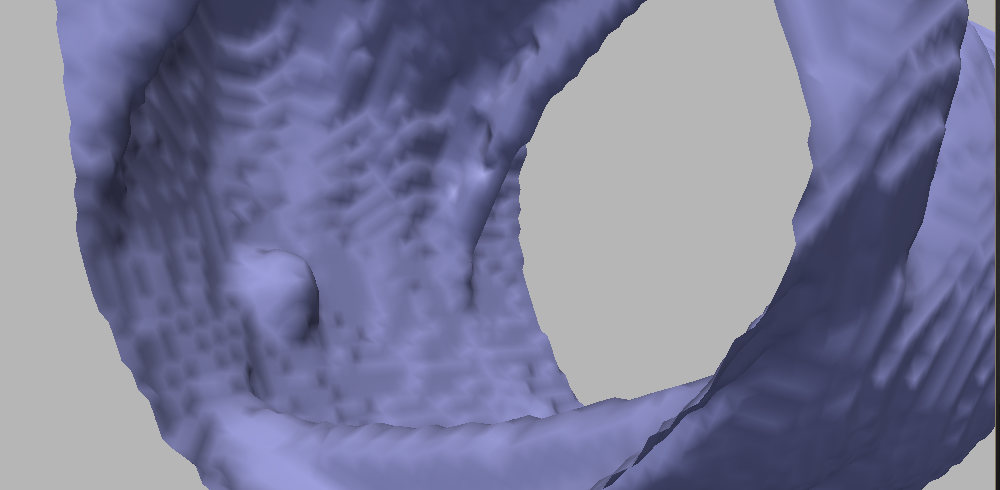

With the mean curvature motion (), the polyps are flattened too fast, as shown in in Figure 5. A suitable variation of the motion by Gaussian curvature,333The motion by Gaussian curvature has several problems with surfaces containing non-convex parts [44]. namely the affine motion

has a better behavior in general, but the results regarding polyp flattening are comparable with the mean curvature.

A classical motion that appears to be well suited for our problem is the motion by minimal curvature [45]. Indeed, polyps have a curve of inflection points all around it, separating its upper and lower sections (see Figure 6). Along this curve, the minimal curvature is , and therefore this section of the polyp does not move (or moves very slowly), so intuitively under this motion the polyps should persist longer. In our application, this evolution yields very good results in terms of both surface smoothing and polyp enhancement.

This PDE can be modified to obtain better results in terms of polyp detection. We now propose a set of modifications that lead us to the proposed smoothing evolution equation, and we show qualitative results to support this claim. The improvement in terms of polyp detection performance is discussed in Section V.

Figure 7 shows the result after a few iterations; comparing to Figure 5, it can be readily seen that this motion achieves a better trade-off in terms of noise reduction and polyp preservation. Figure 8 evidences the difference with a comparative image: the result of the motions by and are shown in gray and in orange, respectively. On the polyp protrusion, the orange surface is above the gray surface, while the opposite is observed in the surrounding area. This shows that the evolution by leads to better polyp enhancement.